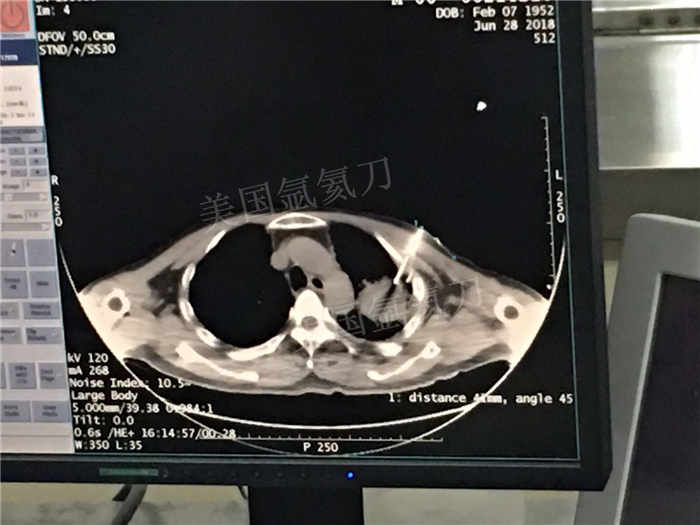

发布人:美国氩氦刀技术官方网站 发布时间:2018/7/5 10:57:23

下一篇:中日友好医院氩氦刀冷冻消融治疗胸膜间皮瘤